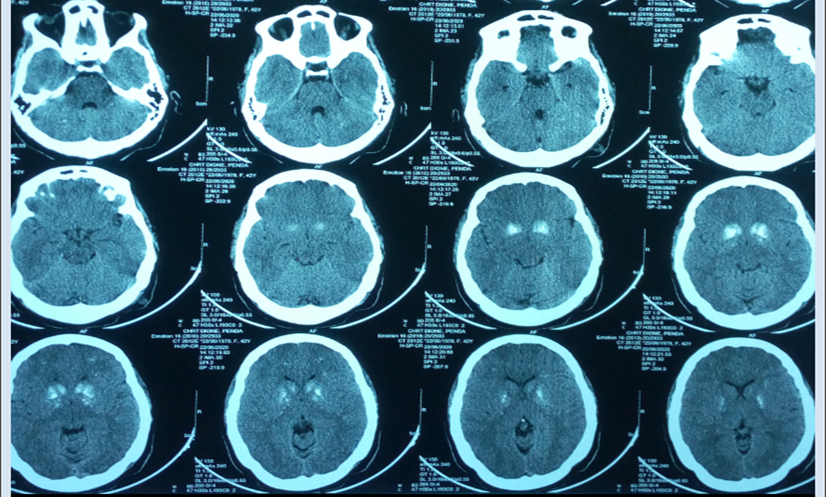

Fortuitous Discovery of a Fahr Syndrome in a Psychiatric Environment

Ibra DIAGNE, Maimouna DIEYE, Khadim SECK, Ndèye Dialé NDIAYE-NDONGO, Aida Sylla

International Journal of Innovative Research in Medical Science·March 7, 2022